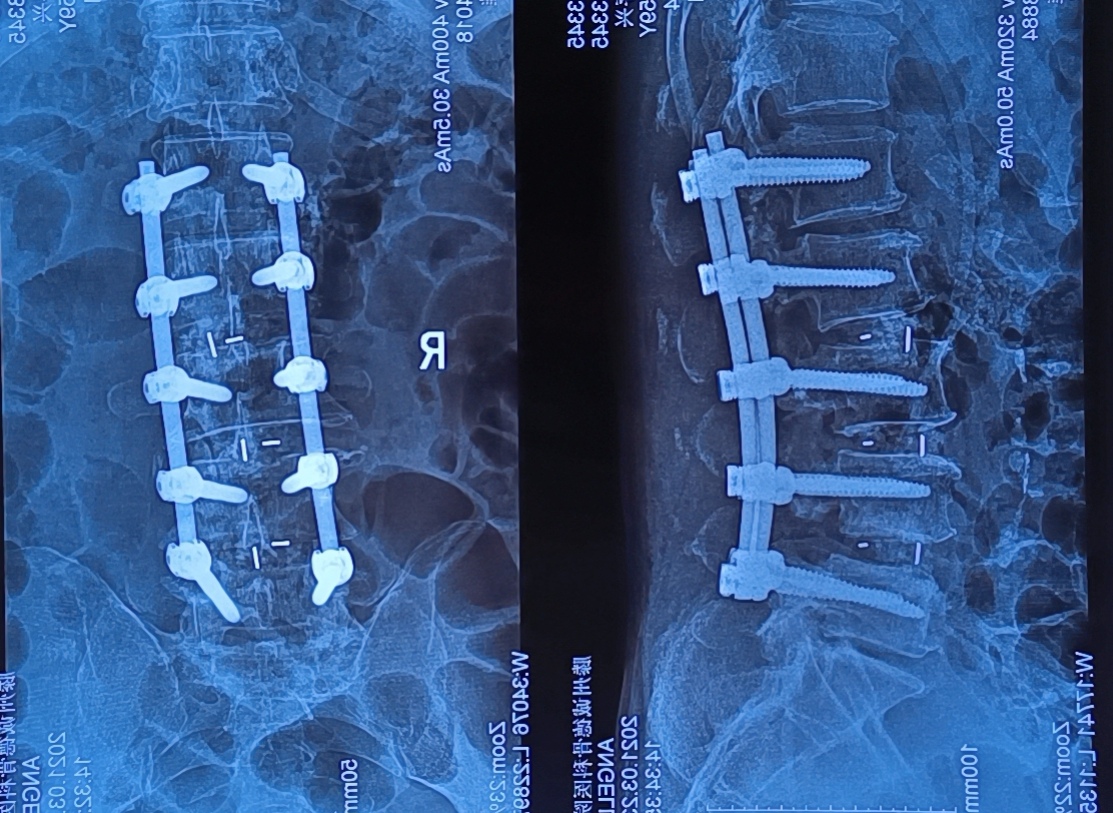

然而、萬幸的是在2020年11月21日,患者來到了滕州誠德骨科醫(yī)院就診,經(jīng)專家查體,確診為腰椎管狹窄癥。與患者溝通后做了腰1-腰5減壓植骨內固定術,術后患者癥狀立刻減輕,術后第三天就可以下地行走。

一個月后復查,患者走路非常自如,秦先生對誠德骨科醫(yī)院的醫(yī)術和服務贊不絕口。